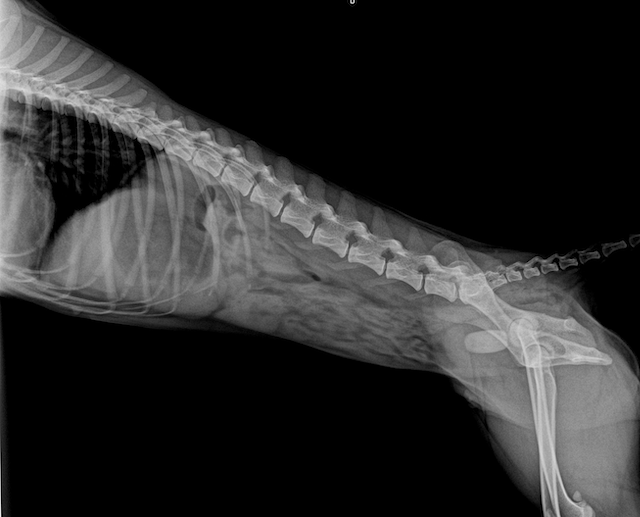

2ヶ月ほど前から血尿があり、かかりつけの病院で治療していましたが良くならず当院でレントゲンの検査をしたところ膀胱に結石があることが分かり、摘出手術を行いました。

📸レントゲン画像